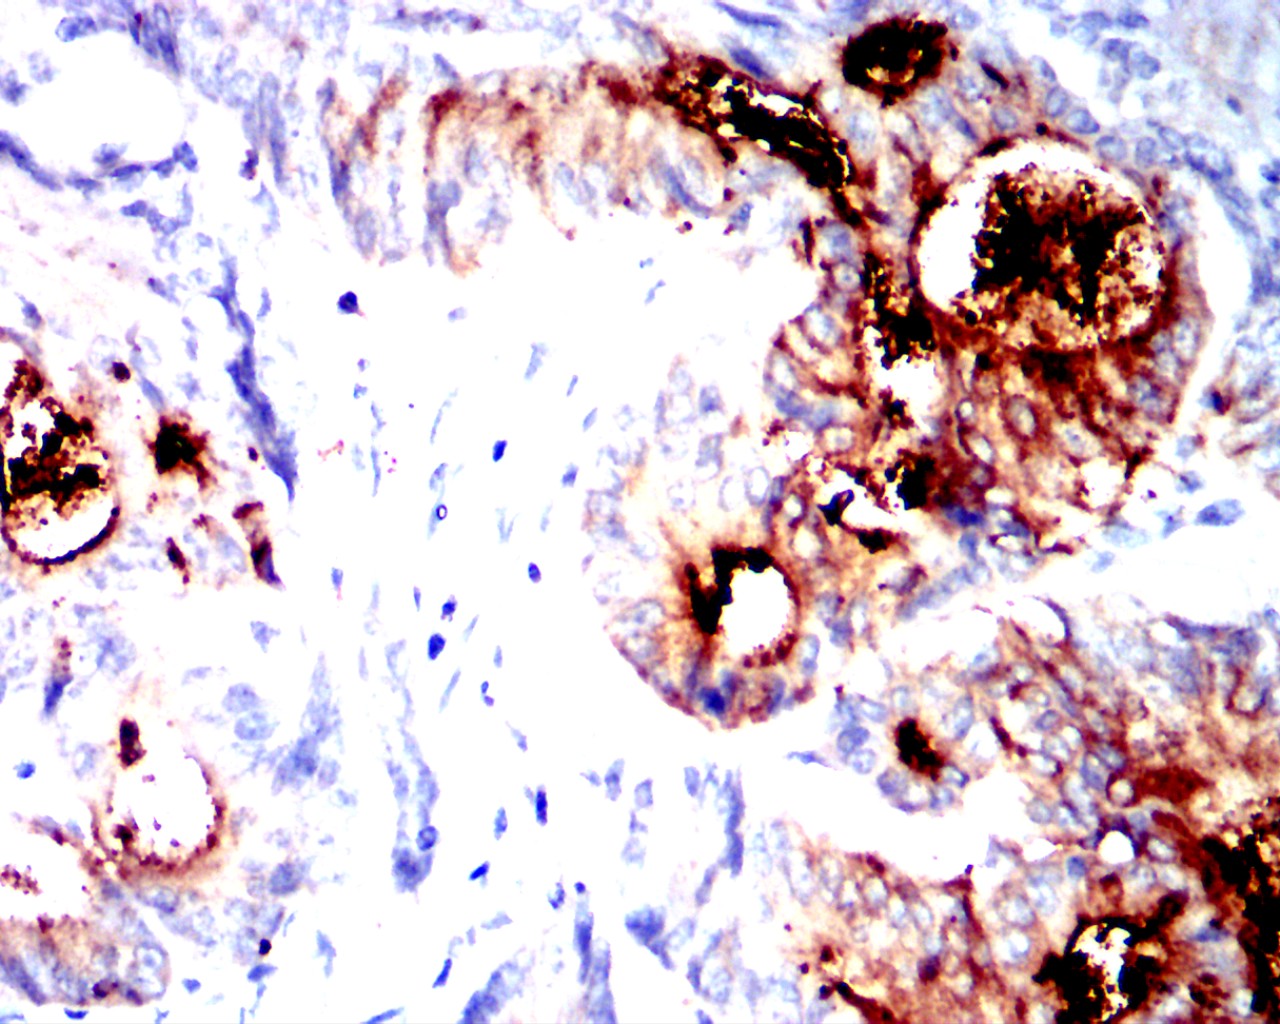

分类: 科研抗体货号: 32454别名: CEA;CD66e应用: IHC反应种属: Human